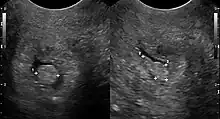

| Cervical polyp on ultrasound | |